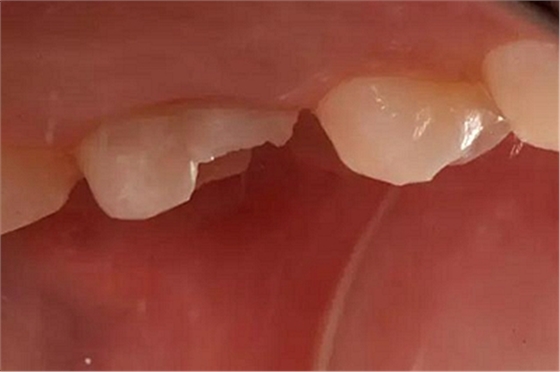

患者女性,55歲,3年前B3纖維樁+鑄瓷全冠修復(fù),一周前牙冠折斷,就診后,發(fā)現(xiàn)纖維樁根管口處折斷,周圍牙齦增生,建議患者行冠延長手術(shù)。首先去除斷端的纖維樁。拍片示牙根長度充足。于是開始冠延長手術(shù)。

因?yàn)槭乔把溃试摶颊邔硇迯?fù)體邊緣必須為齦下,所以3個月后再行修復(fù)。以下為手術(shù)前照片。

以下為術(shù)中照片。

內(nèi)斜切口,頸圈組織,改良垂直褥式縫合。